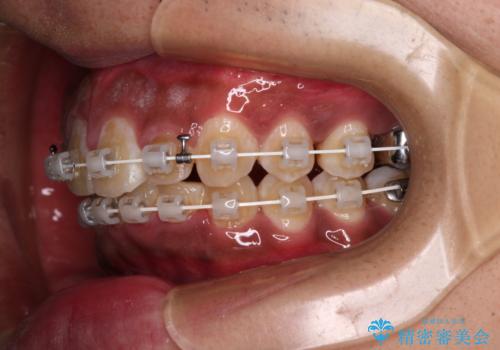

- 審美装置

抜歯は行わず、補助装置を用いて上顎歯列全体を後方移動させ、ワイヤー装置にて奥歯の咬み合わせを改善していくこととしました。

正面や横から見た印象が同じで用であっても、奥歯の咬み合わせが理想的であるかどうかによって、治療の難易度は大きく異なります。

こちらの方も難易度のやや高い状態で、2年以上の期間が予想されましたが、想定通りの2年強で治療を終えることができました。